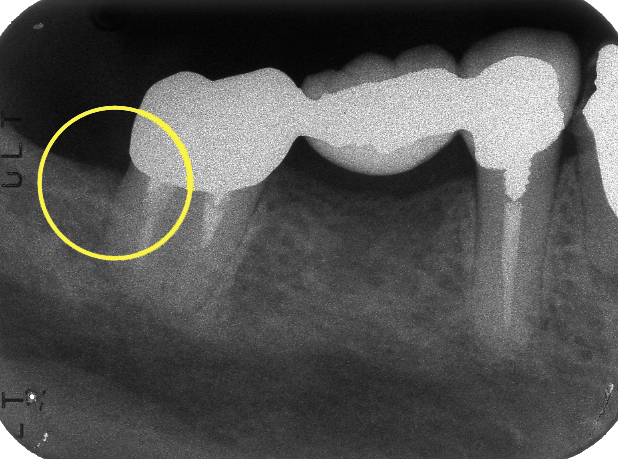

治療後1年経過時のレントゲン写真です。付着していた歯石や,不適合な被せ物はなくなり,溶けていた歯槽骨が再生しているのが分かります。

歯周ポケットも3mm以内と浅くなり,健康な状態を取り戻すことが出来ました。